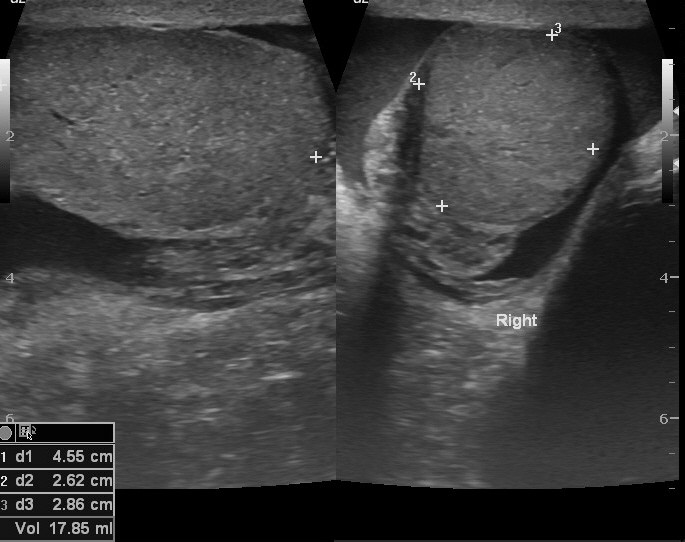

Badanie umożliwia ocenę jąder, najądrzy, osłonek jąder oraz struktur znajdujących się w obrębie worka mosznowego. Pozwala także wykryć obecność żylaków powrózka nasiennego, które mogą mieć znaczenie kliniczne i wpływać na dalsze postępowanie diagnostyczne lub lecznicze.

USG jąder jest jednym z podstawowych badań obrazowych wykorzystywanych w diagnostyce zmian w obrębie moszny. Dzięki niemu lekarz może lepiej ocenić przyczynę dolegliwości i zdecydować o dalszych krokach.